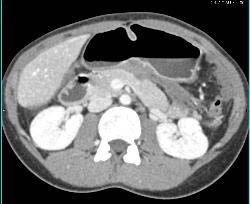

Desmoid Tumors and Fluid in Lesser Sac Pushing on the Stomach